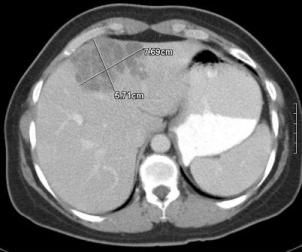

Laboratory test results revealed a microcytic anemia (hemoglobin level, 111 g/L; mean corpuscular volume, 75.1 fL) and a normal leukocyte count (5 x 106/L), with 17.5% eosinophils. Serum liver enzyme levels were normal. The patient’s erythrocyte sedimentation rate (ESR) was 105 mm/h, and her serum IgE level was 550 IU/mL (normal range, 0 to 100 IU/mL). A CT scan of the abdomen showed multiple cystic areas in the liver (Figure 1). Test results for hepatitis, malaria, and tuberculosis were negative. Results of a test for Toxocara canis IgG were negative.